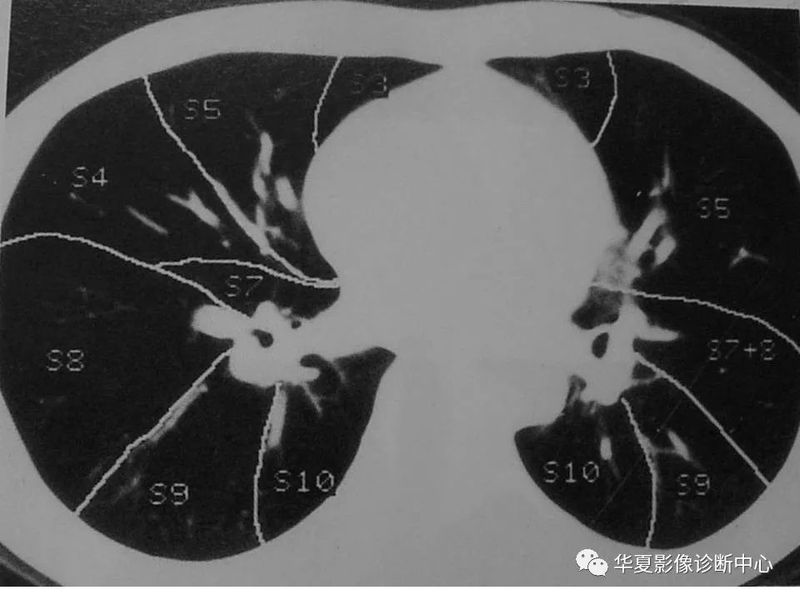

干货 | 汇总胸部CT读片扫盲知识,看懂胸部CT不再难